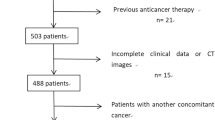

In this retrospective study, we included 49 patients with occult PM and 49 control patients (without PM) who underwent preoperative CT and subsequent surgery between January 2016 and December 2018. Clinical information and CT semantic features were collected, and CT radiomics features were extracted. A predictive clinical-CT model was created using multivariate logistic regression. The least absolute shrinkage and selection operator algorithm and logistic regression were used for constructing 2D and 3D radiomics models. These models were validated with an external cohort (n = 30). Receiver operating characteristics curve with area under the curve (AUC), sensitivity, and specificity were used to evaluate predictive performance.